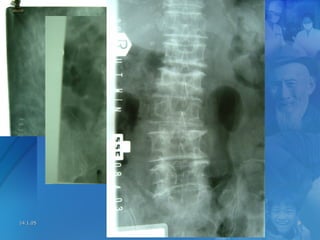

Low Trauma FracturesLow Trauma Fractures

14.1.0514.1.05 OsteoporosisOsteoporosis 88